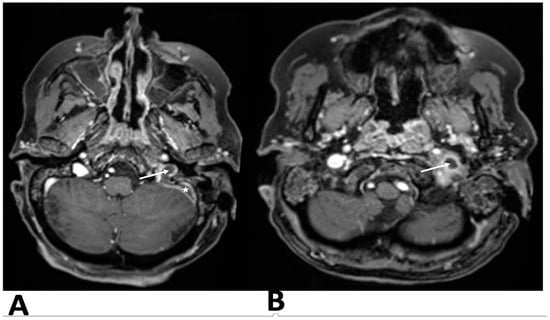

After contrast administration, the left jugular bulb and sigmoid sinus were not opacified, suggesting acute thrombosis at the proximal end of the jugular vein and sigmoid sinus. Brain and skull base magnetic resonance imaging (MRI) and magnetic resonance venography (MRV) confirmed temporal bone inflammation, sigmoid sinus thrombosis extending to the internal jugular vein, jugular vein thrombophlebitis, and no other intracranial complications (Figure 2).

Figure 2. T2-weighted axial section at the level of the jugular foramen hyperintense inflammatory tissue in the left mastoid. (A)The flow void is absent in sigmoid sinus (asterisk) and the jugular bulb (arrow), which is hypoplastic compared with the contralateral side, JV thrombosis with EJV thrombophlebitis (B).